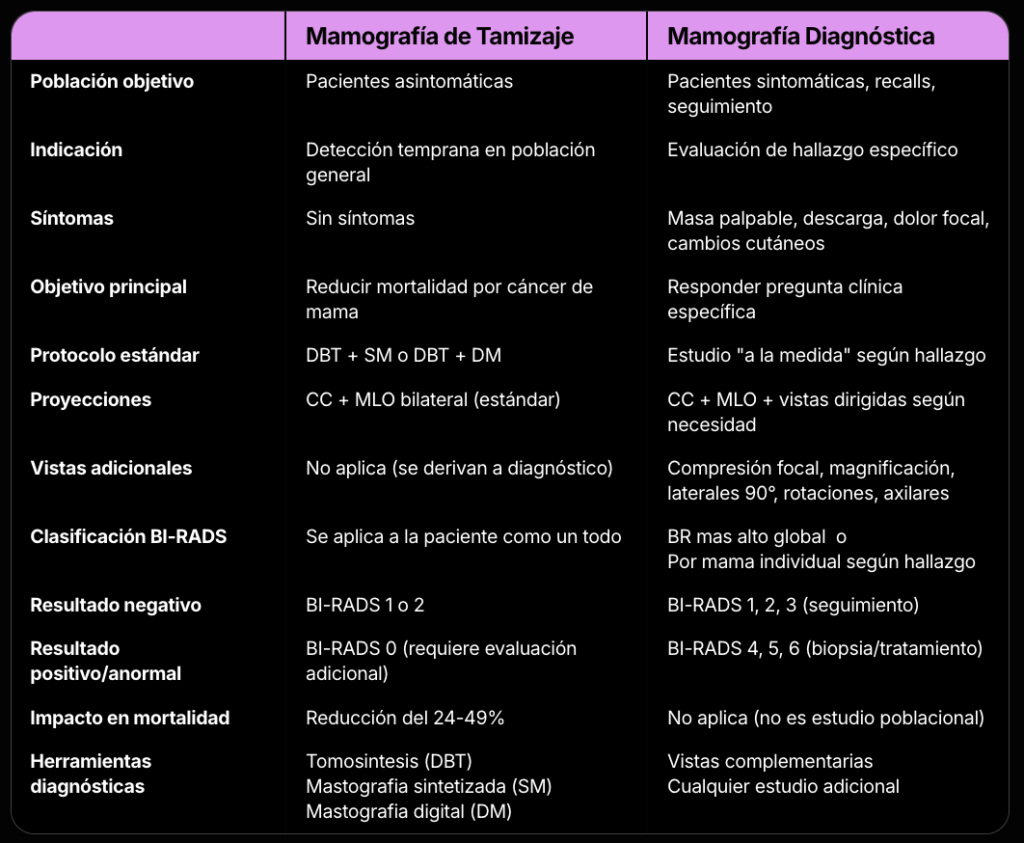

“Mamografía Post-Procedimiento para Colocación de Marcador”.

Esta evaluación se usa para confirmar la posición de un clip de biopsia.

A diferencia de las categorías 0-6, esta no lleva un código numérico y exime al examen de los requisitos de auditoría médica estándar, reconociendo que su fin es técnico y documental, no diagnóstico.